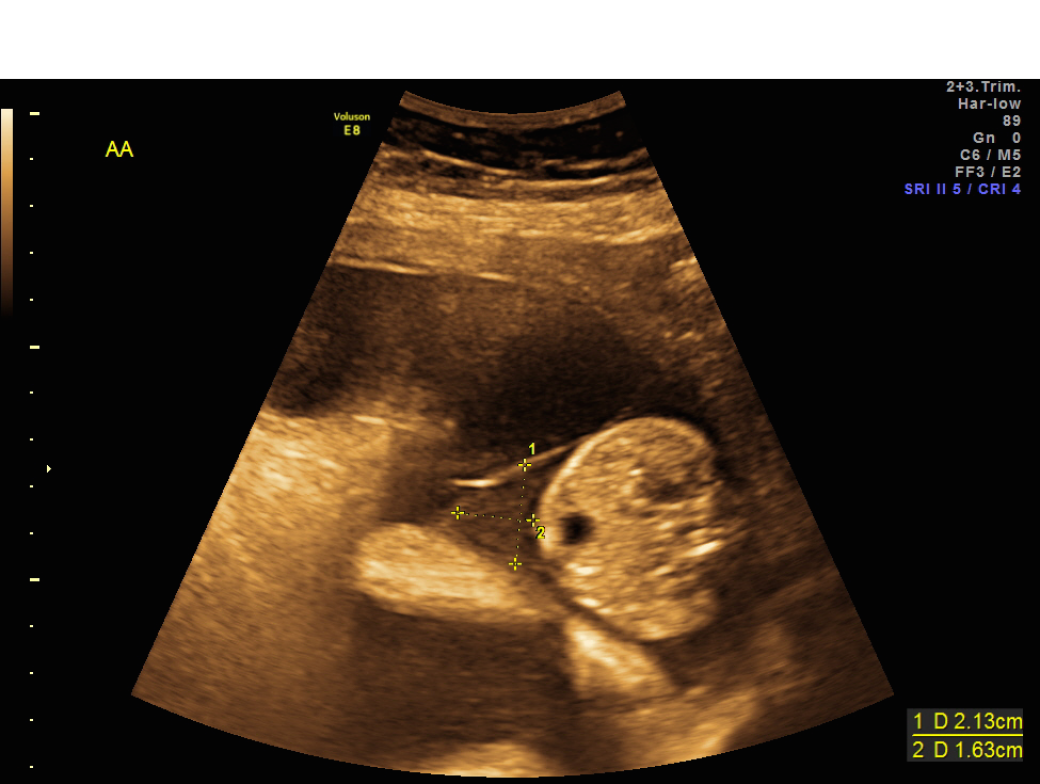

Sonographic image of the placenta of twin A at 13 weeks of gestation of Is It Dangerous For Twins To Share A Placenta in pregnancies with one placenta and two amniotic sacs, you will definitely have identical twins. Additionally, when your babies share a placenta,. — it’s possible for twins to share the same chorionic and amniotic sacs or have their own. — with identical twins, it's possible for a blood vessel in a shared placenta to result in one. Is It Dangerous For Twins To Share A Placenta.